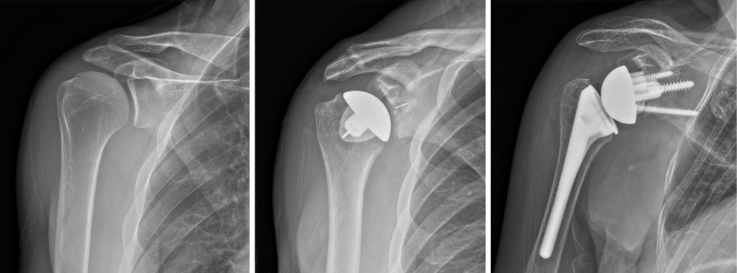

There are two primary types of shoulder replacements: anatomic and reverse. Anatomic shoulder replacement mirrors the shoulder's natural structure, while reverse shoulder replacement alters the joint mechanics to benefit patients with severe rotator cuff damage. The rationale for choosing either procedure often hinges on the patient’s specific condition, their anatomical needs, and overall health. As populations age and physical activity levels change, there has been a noticeable increase in the prevalence of shoulder replacements within orthopedic surgery practices. This rise reflects advancements in surgical techniques and artificial implant technologies, providing new options for those suffering from debilitating shoulder ailments.

Anatomic shoulder replacement, often utilized for patients with arthritis or trauma affecting the glenohumeral joint, involves replacing the damaged portions of the shoulder with implants that closely mimic the natural anatomy. The procedure typically utilizes a ball-and-socket implant system, wherein the humeral head is replaced with a prosthetic ball, while the socket (the glenoid) is lined with a polyethylene implant. The surgical technique requires precise alignment to ensure optimal shoulder mechanics, which allows for a more natural range of motion post-operation.

Conversely, reverse shoulder replacement is primarily indicated for patients with rotator cuff deficiency, severe arthritis, or failed prior shoulder surgeries. This procedure involves an inversion of the traditional implant design—here, the ball is attached to the shoulder socket, and a concave socket is placed on the upper arm bone (humerus). The reverse configuration redistributes the forces around the shoulder joint and employs different muscular dynamics, thus compensating for the lack of functional rotator cuff muscles. The surgical technique also necessitates careful consideration of patient anatomy, as the procedure aims to provide stability and improved range of motion in the affected joint.